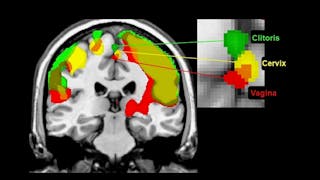

In einer funktionellen MRT-Studie reagierte bei Frauen, die ihren Gebärmutterhals stimulierten, der gleiche Teil ihres Gehirns wie bei der Stimulation ihrer Klitoris oder Vagina. Sie berichteten auch, dass sie jede Region deutlich spüren konnten. Der Beitrag des Gebärmutterhalses zum Orgasmus wird in populären Medien beschrieben und einige Frauen berichten, dass zervikal stimulierte Orgasmen andere Qualitäten haben als klitoral oder vaginal stimulierte Orgasmen.